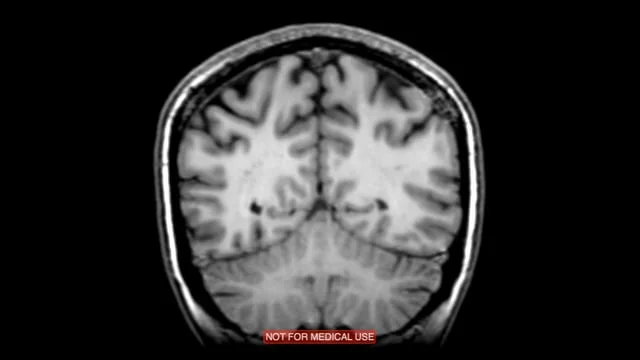

Digitally processed footage from an fMRI scan of my very own brain. Mirroring and colourizing abstracts and combines the recognizable forms into a strange and foreign, yet utterly intimate, look beyond surface skin.

Footage processed in OsiriX medical imaging software and further edited in Final Cut Pro X. The fMRI scan is courtesy of the University of Michigan Functional MRI Laboratory.

Digitally processed footage from an fMRI scan of my very own brain. Different computerized filters, angles, and scans investigate isolating and alienating technological views of a very intimate symbol of self-hood: the brain.